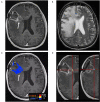

In the follow-up treatment of high-grade gliomas (HGGs), differentiating true tumor progression from treatment-related effects, such as pseudoprogression and radiation necrosis, presents an ongoing clinical challenge. Conventional MRI with and without intravenous contrast serves as the clinical benchmark for the posttreatment surveillance imaging of HGG. However, many advanced imaging techniques have shown promise in helping better delineate the findings in indeterminate scenarios, as posttreatment effects can often mimic true tumor progression on conventional imaging. These challenges are further confounded by the histologic admixture that can commonly occur between tumor growth and treatment-related effects within the posttreatment bed. This review discusses the current practices in the surveillance imaging of HGG and the role of advanced imaging techniques, including perfusion MRI and metabolic MRI.